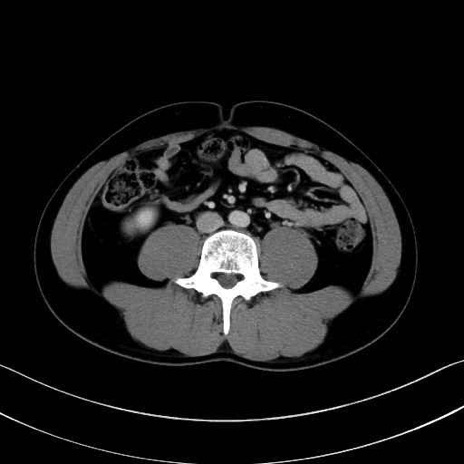

大腰筋 (Psoas major)

腸骨筋 (Iliacus)